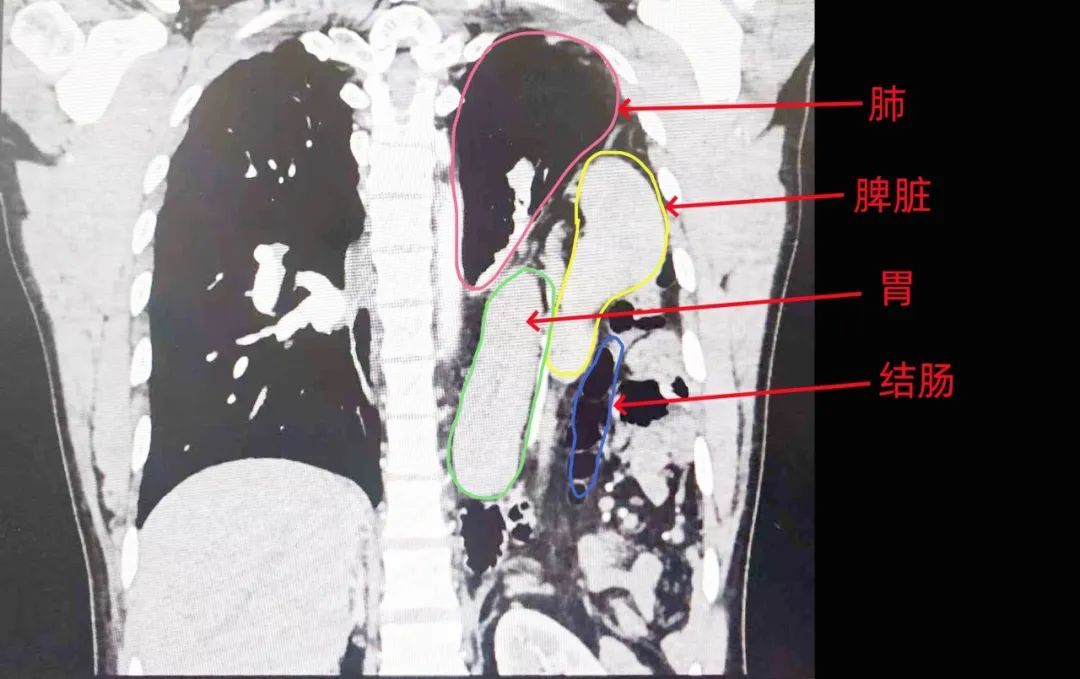

王先生腹腔内的脏器大量挤入胸腔,导致心脏、左肺受到严重压迫,左侧膈疝!

市民王先生的医学检查影像

很显然,王先生的脾胃肠已经全部乱入到了他的胸腔里!

为保险起见,医生们先用胸腔镜进行探查。果然,王先生的腹部器官几乎都“跑路”了,整个脾脏、胃、大网膜、结肠大部分都疝入了胸腔,与胸腔膈肌紧密粘连,情况比想象中复杂。此外,医生们还不出意外地在王先生的左侧膈肌上发现了一个8-10厘米的裂孔,这就是王先生腹部内脏跑路的通道。